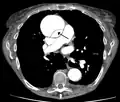

Computed tomography

Computed tomography angiography is a fast, non-invasive test that gives an accurate three-dimensional view of the aorta. These images are produced by taking rapid, thin-cut slices of the chest and abdomen, and combining them in the computer to create cross-sectional slices. To delineate the aorta to the accuracy necessary to make the proper diagnosis, an iodinated contrast material is injected into a peripheral vein. Contrast is injected and the scan performed using a bolus tracking method. This type of scan is timed to injection to capture the contrast as it enters the aorta. The scan then follows the contrast as it flows through the vessel. It has a sensitivity of 96 to 100% and a specificity of 96 to 100%. Disadvantages include the need for iodinated contrast material and the inability to diagnose the site of the intimal tear.

CT with contrast demonstrating aneurysmal dilation and a dissection of the ascending aorta (type A Stanford)- Chest CT with descending (type B Stanford) aortic dissection (red circle)

Type A dissection with pericardial effusion as a result.